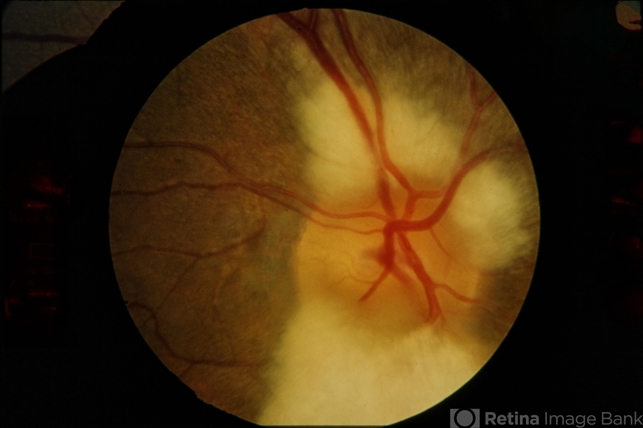

- Myelinated Nerve Fiber Layer

- myelinated nerve fiber layer, optic nerve

- Embryonic myelin surrounding optic nerve.